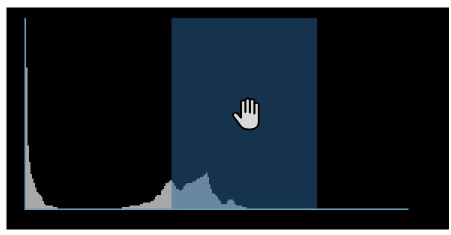

Histogram¶

A windowing histogram is a graphical representation of the distribution of intensity values in an image. It displays the number of pixels at each intensity level, allowing users to adjust the brightness and contrast by setting a window around a range of intensity levels. By adjusting the position and width of the window, the user can optimize the image for their specific needs and better visualize the image features.

To change the window width, press and drag the left or right edge of the rectangular area representing the window.

To change the position or the window center, press and hold on the rectangular area and drag in the desired direction.